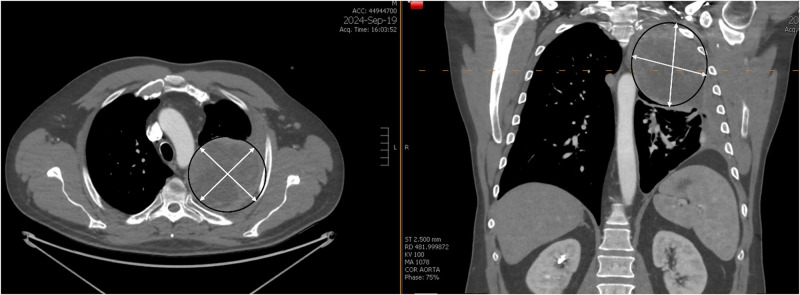

Epidural anesthetic techniques for postoperative analgesia are rarely considered in spinal surgery, and high thoracic epidural analgesia (TEA) is considered medically risky. We present a successful case of surgical retrograde placement of a thoracic (T6-T7) epidural catheter under direct surgical visualization via T2 laminectomy in a patient who underwent combined thoracotomy and spinal surgery. TEA was confirmed by epidurogram, provided adequate postoperative pain relief, and the patient was discharged home three days post-surgery.